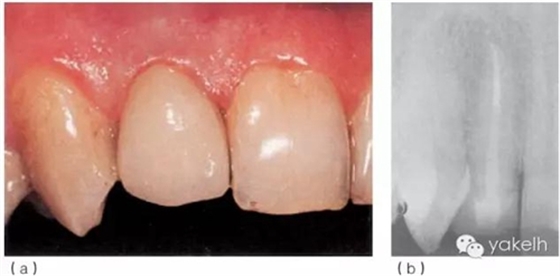

¤¤首先,使用超聲器械清理根管,確保樁道內(nèi)的根管壁上沒有牙膠及根管封閉劑殘留;通過試戴,選擇合適的纖維樁(圖6.3.5a);酒精擦拭樁道后,進行酸蝕、沖洗、干燥;使用復合樹脂粘結(jié)劑粘樁(圖6.3.5b),光固化(圖6.3.5c);在樁及剩余牙體表面涂布牙本質(zhì)粘結(jié)劑,逐層堆塑樹脂核;樹脂核完成后,即刻行冠部預備(圖6.3.5d);制取印模,使用術前模型制作丙烯酸臨時冠;拍攝術后X線片(圖6.3.5e);2周后復診,粘固永久性全冠(圖6.3.6a);1年后復查,患者無不適,根尖X線片顯示患牙根尖周組織正常(圖6.3.6b)。

圖6.3.5

(a)修復過程中使用橡皮障隔離患牙。在選好的纖維樁上放置橡皮止動片,確保纖維樁到達根管充填材料的冠方。

(b)使用特制輸送器把粘結(jié)劑注入樁道底部,防止形成空隙。

(c)去除多余粘接劑,進行光固化。

(d)同時進行牙冠預備。

(e)12根管再治療,樁核就位后X線片。

圖6.3.6(a)粘固永久性全冠。(b)12術后1年復查X線片。